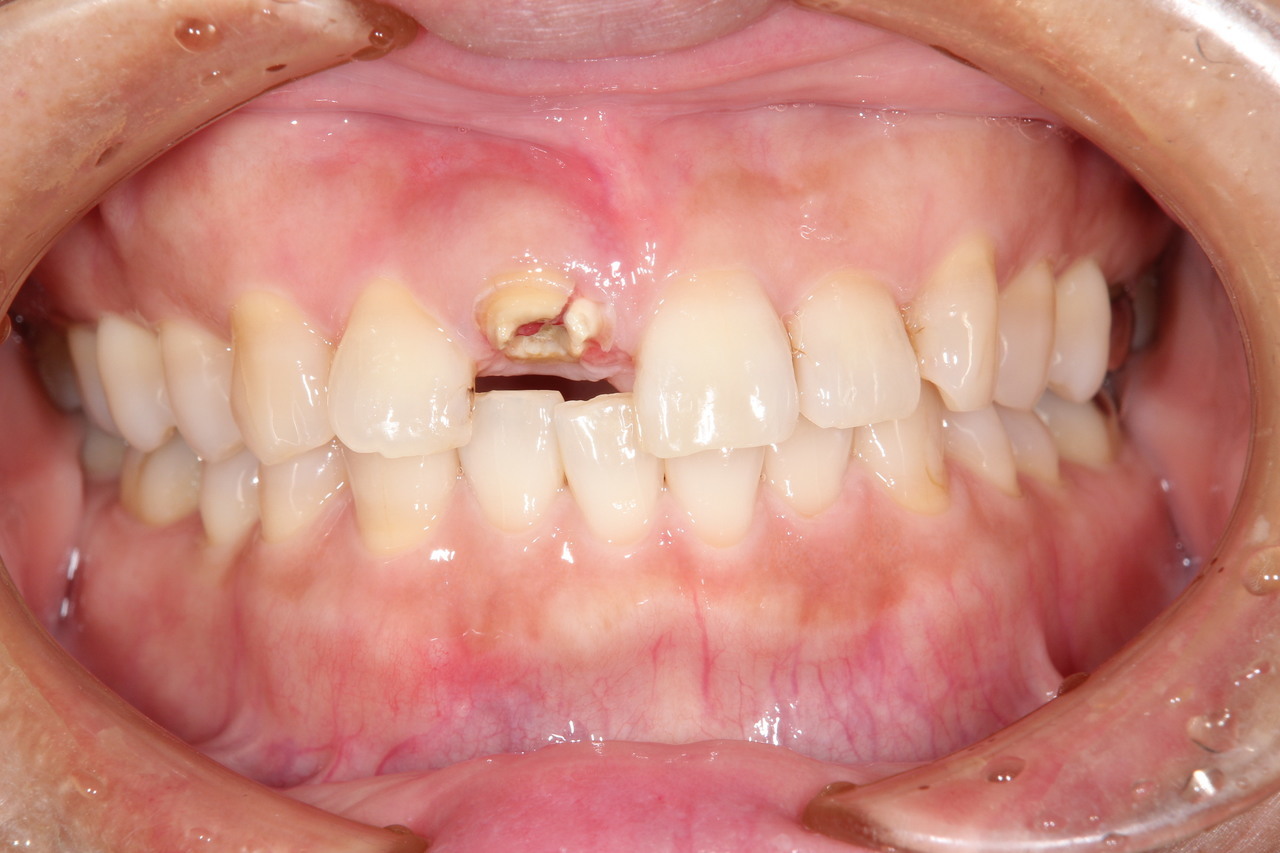

前歯インプラント(美しさを重視した場合は、ジルコニアでセメント固定がお勧めです。前歯の場合は、歯肉の形をシャープできれいな形にする為、仮歯が必要です。)

(下田市在住 女性)

治療の流れ

前歯破折

神経を取って差し歯にしていた歯根が破折したため、抜歯することになりました。

前歯インプラント土台

前歯部の審美領域は、白い土台など、より綺麗に見せるオプション費用が追加になります。

前歯インプラント

最終的な被せ物を装着すると、隣の天然歯と見分けがつかない綺麗な仕上がりになりました。

インプラント手術:250,000円

静脈内鎮静法:0円

仮歯:50.000円

ジルコニアアバットメント:120,000円

前歯用プレミアムジルコニア:150,000円

総額:570,000円+税